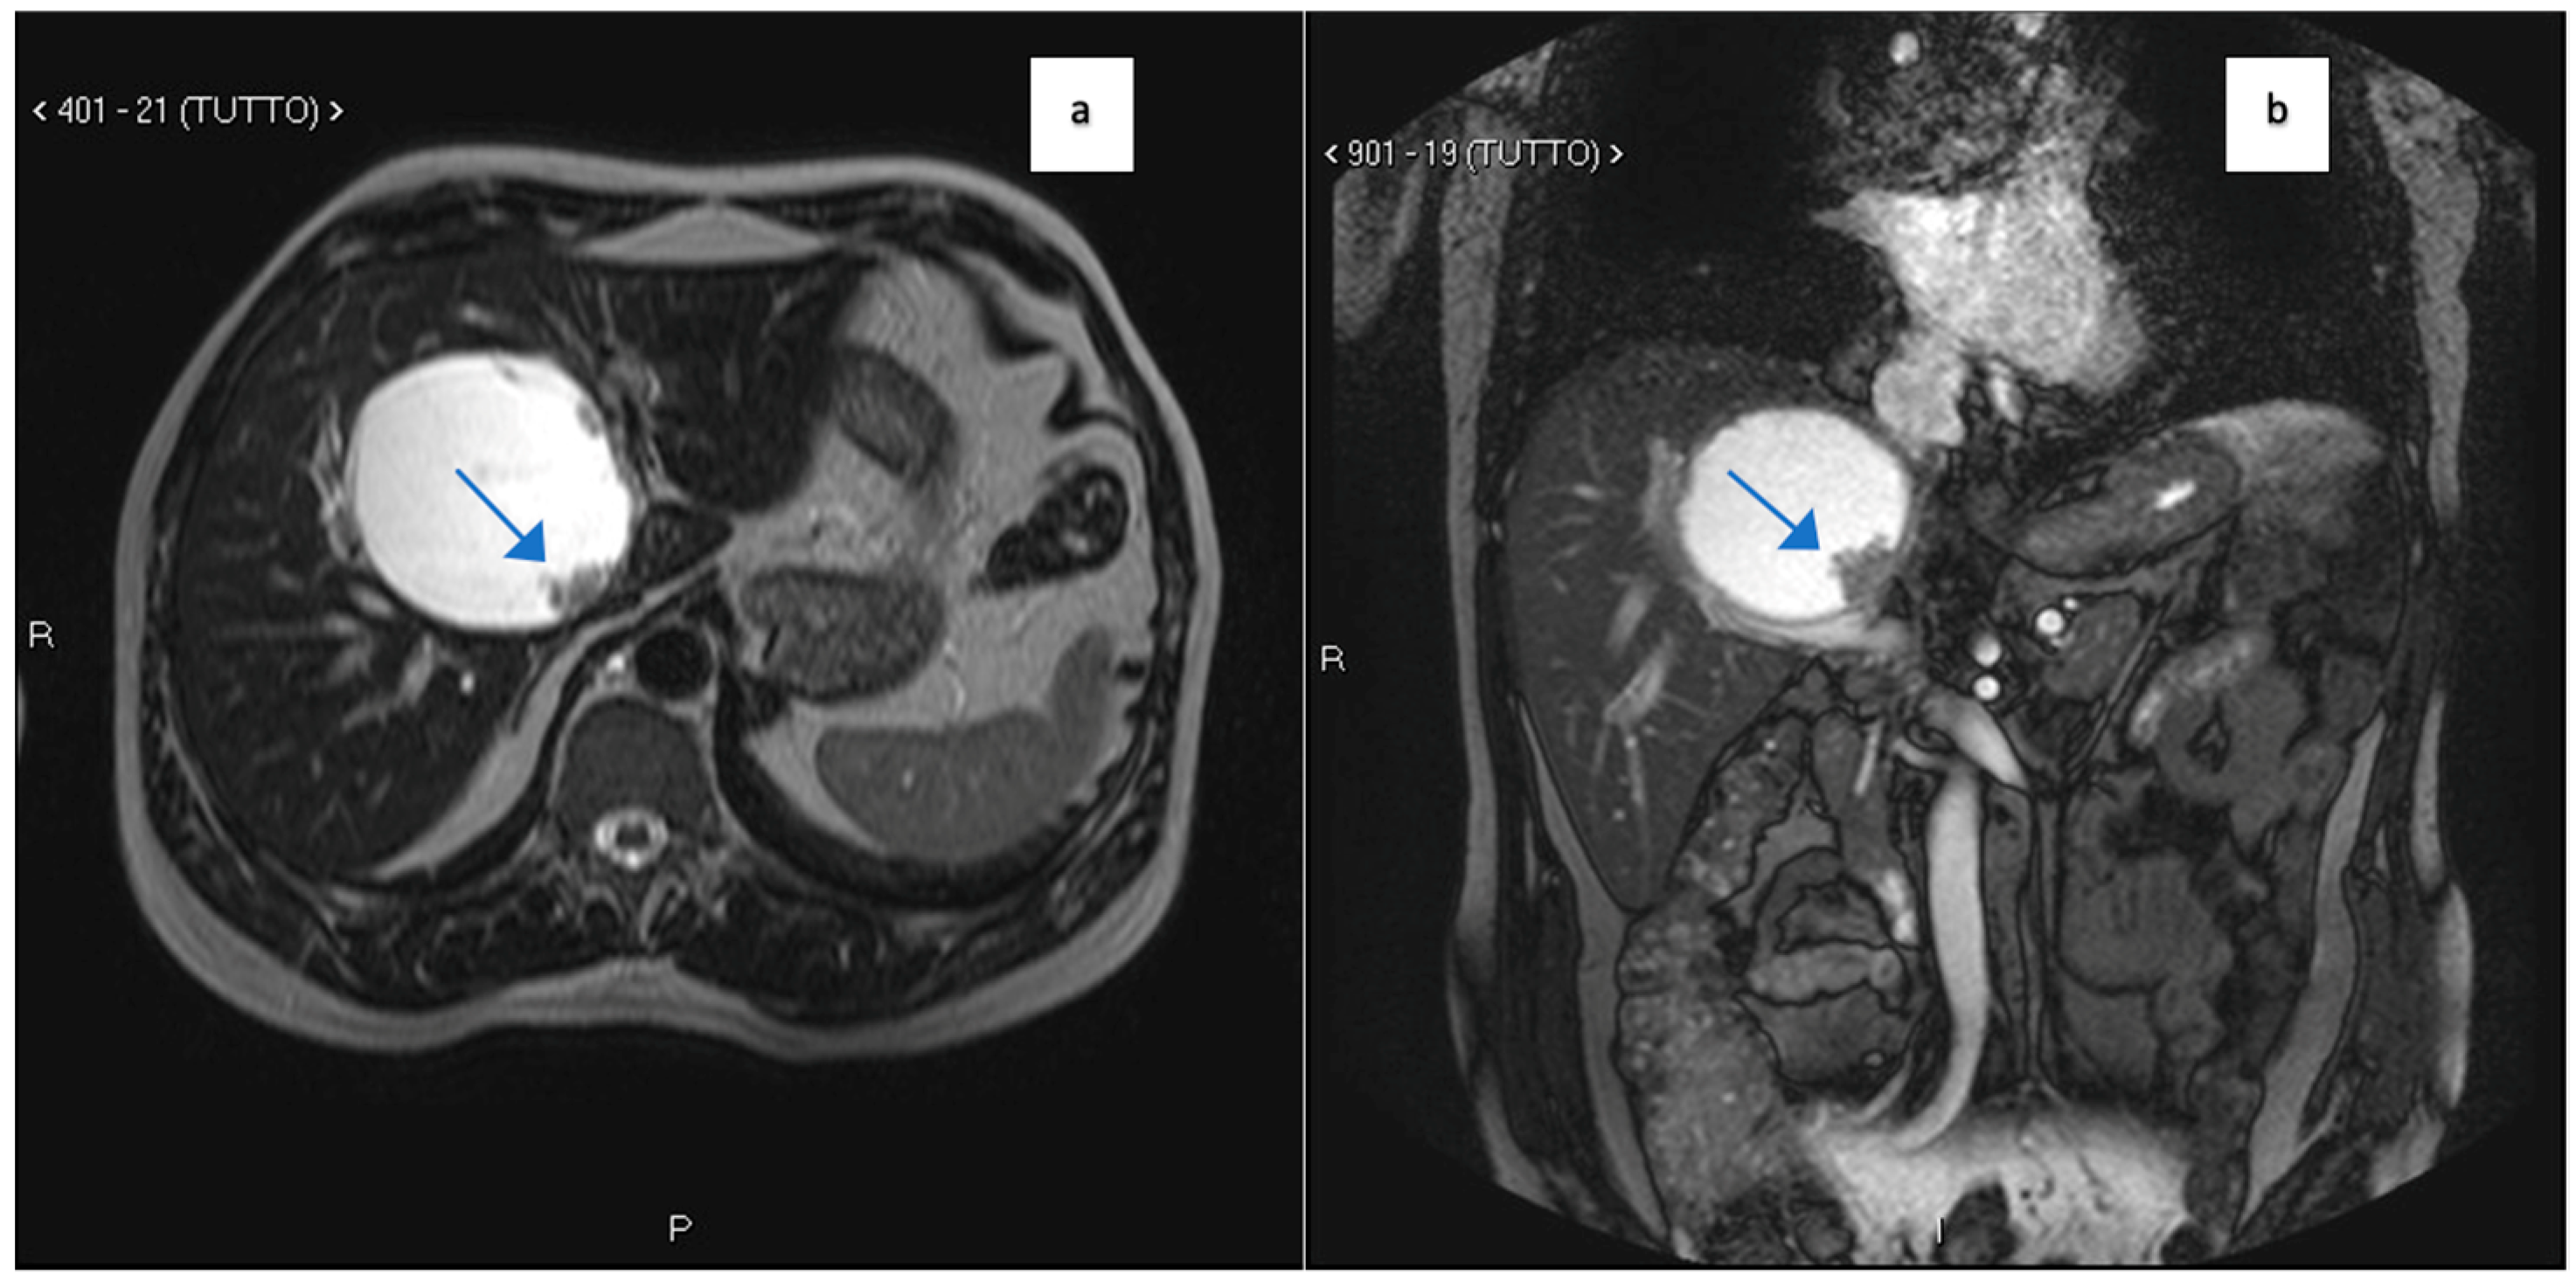

2. Case Report 1

| Clinical Presentation | Incidental discovery of an 8 × 8 × 9 cm hepatic cyst | Presented with dyspnea, vomiting, jaundice, fever |

| Tumor Characteristics | Large cystic mass, thin walls, internal septa, papillary projections, enhancing solid components | Large lesion in left hepatic lobe, hyperintensity in T2-weighted images, restricted diffusion, contrast enhancement |